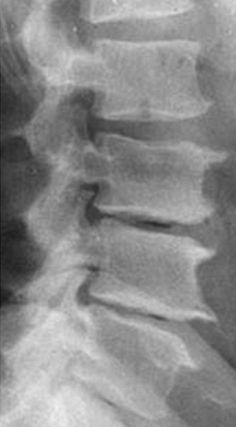

Questa condizione viene indicata al riguardo della colonna vertebrale.![]() |

![]() |

Indicano l'avvicinamento di due corpi vertebrali per degenerazione del disco vertebrale, che diventa più sottile.

Conflitti recidivanti di inadeguatezza a sopportare il carico, sentirsi schiacciati.